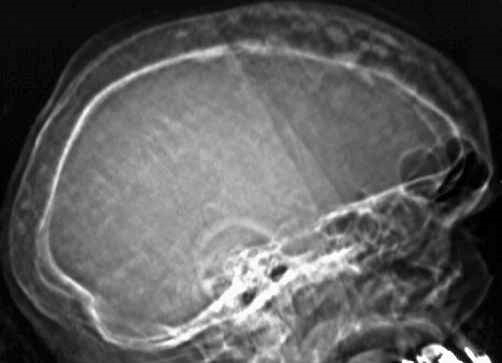

Los cambios radiográficos son patognomónicos, y suelen llevar al diagnóstico. La Fig. 80-2 muestra un húmero; la Fig. 80-3 una vértebra, la Fig. 80-4 una pelvis, y la Fig. 80-5 un cráneo afectados por la enfermedad de Paget; la Fig. 80-6 es el estudio tomográfico del mismo cráneo.

Fig. 80-5. Vista de perfil de un cráneo pagético: obsérvese el grosor de la calota y la densificación de la tabla interna.